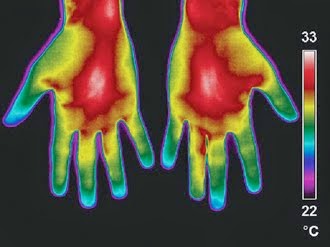

كل موجة كهرومغناطيسية نستطيع معمليا رصدها ووصفها ومعرفة ترددها وطولها الموجي ومقدار الطاقة التي تحمله، بالتالي إذا كان جسم الإنسان يصدر موجاتكهرومغناطيسية فبالتأكيد يمكن رصدها. مثبت علميا أن جسم الإنسان يُصدر موجات تحت حمراء، وهي الحرارة التي يصدرها الجسم ويمكن رصدها بواسطة كاميرا حرارية، كما في الشكل أدناه. هذه الحرارة ناتجةعن العمليات الكيميائية التي تحدث في الجسم أثناء حرق الغذاء وانتقال الدم والحركة الميكانيكية للأعضاء، مع التنبيه على أن هذه الألوان التي تظهر في الصورة ليست ألوان حقيقة، لأن الأشعة تحت الحمراء غير مرئية، وهنا تتدخل البرامج الحاسوبية في إعطاء الموجات المختلفة ألوان مختلفة لتسهيل تميزها بالنظر.